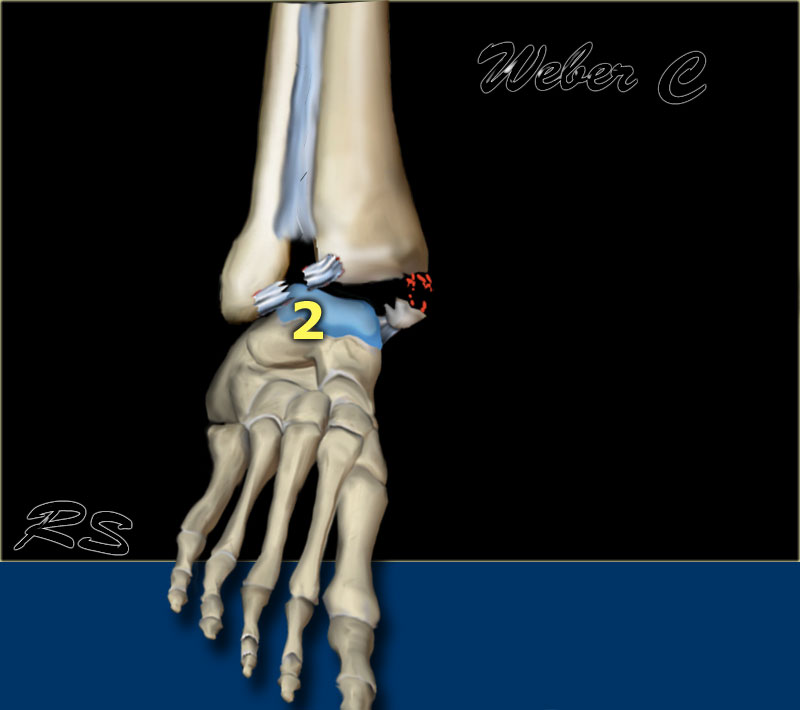

Here we see the different stages in the axial plane.

- Medial avulsion fracture or rupture of the collateral band

- Rupture of the anterior syndesmosis

- Suprasyndesmotic rupture of the fibula due to rotation

- Gãy mắt cá sau hoặc đứt dây chằng chày mác sau

Scroll through the images.